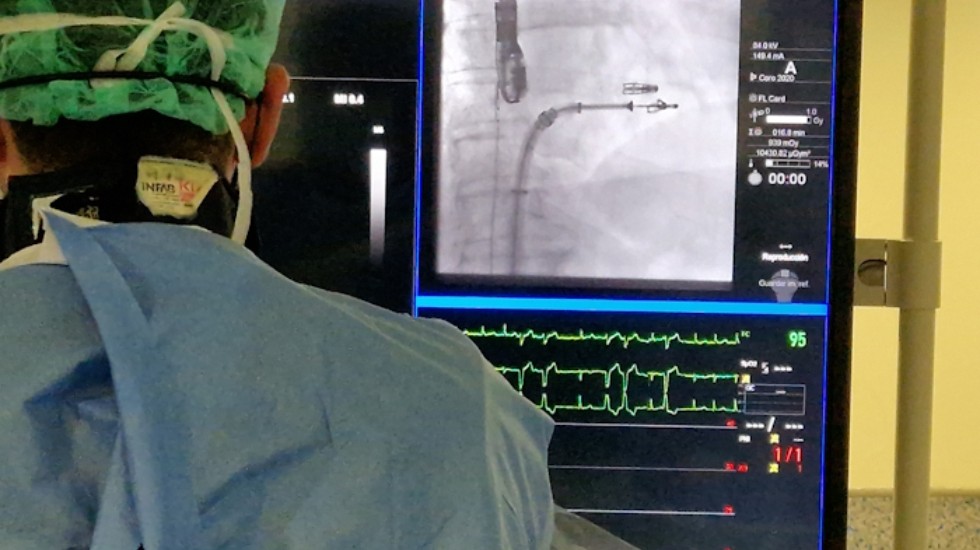

Oviedo, 15 de octubre de 2025 – El servicio de cardiología del Hospital Universitario Central de Asturias (HUCA) ha realizado con éxito el primer procedimiento en España guiado con la sonda VeriSight Pro 3D de Philips, una innovación pionera en ecocardiografía intracardíaca (ICE). “El nuevo catéter nos ha permitido tratar la válvula tricúspide de una forma mucho más precisa”, ha explicado el doctor Pablo Avanzas, director del Área de Gestión Clínica del Corazón del HUCA, en una rueda de prensa realizada en el hospital asturiano.

El 14 de octubre se trataron en el HUCA tres pacientes portadores de una misma patología, la insuficiencia tricúspide grave. Se realizaron las tres intervenciones, implantando varios dispositivos Triclip, guiado con la nueva tecnología, de forma exitosa y sin complicaciones. En comparación con la ecografía transesofágica (ecografía utilizada de forma estándar en el momento actual), la nueva sonda mostró unas imágenes de mejor calidad, lo que facilitó el tratamiento de las mismas mediante la terapia de aproximación borde a borde.

El catéter VeriSight Pro ofrece imágenes 3D en tiempo real directamente dentro del corazón, ayudando a los médicos a realizar procedimientos con mayor eficacia y seguridad: “Esto se traduce en una mayor precisión a la hora de guiar los procedimientos estructurales, como el cierre de comunicaciones interauriculares, la reparación de válvulas o la implantación de dispositivos intracardiacos, mejorando la seguridad y la eficacia de las intervenciones”, según el director del Área del Corazón.

El doctor Avanzas y su equipo han podido evaluar la anatomía, guiar la colocación de dispositivos y confirmar los resultados del procedimiento, todo ello desde un único punto de acceso.